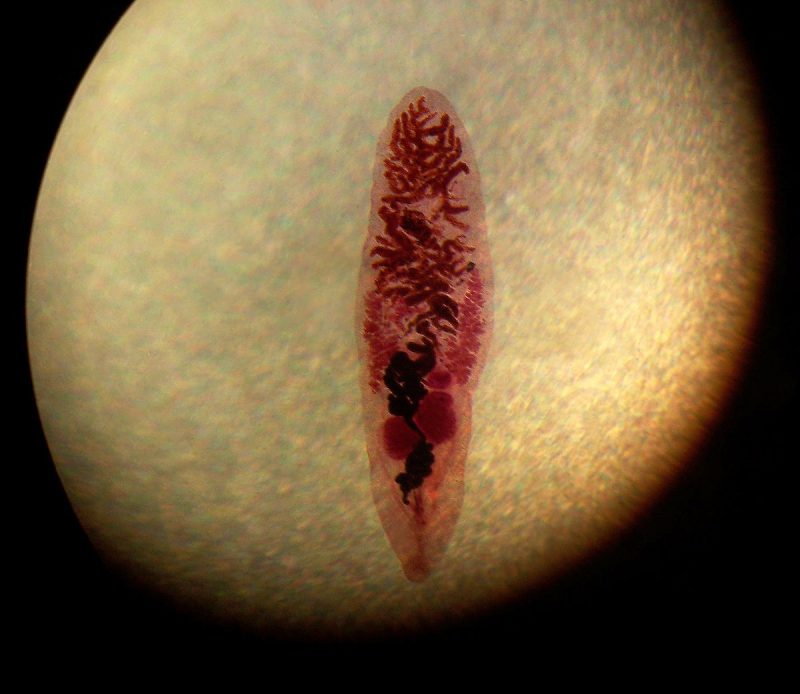

Причиной болезни является червь —, сосальщик dicrocoelium dendriticum из семейства двуустовых. Длина взрослой особи варьируются от 5 до 15 миллиметров, а ширина от 1 до 3 миллиметров. Среда обитания в организме конечного хозяина это желчный пузырь, желчевыводящие протоки и печень.

Проникая в эти органы, червь крепится многочисленными присосками, которые расположены по всему телу паразита, начинает активно питаться и размножаться. При несвоевременной диагностике заболевания и отсутствии лечения, паразиты наносят существенный вред внутренним органам своего хозяина. Проявляется яркая симптоматика заболевания, самочувствие пациента ухудшается.